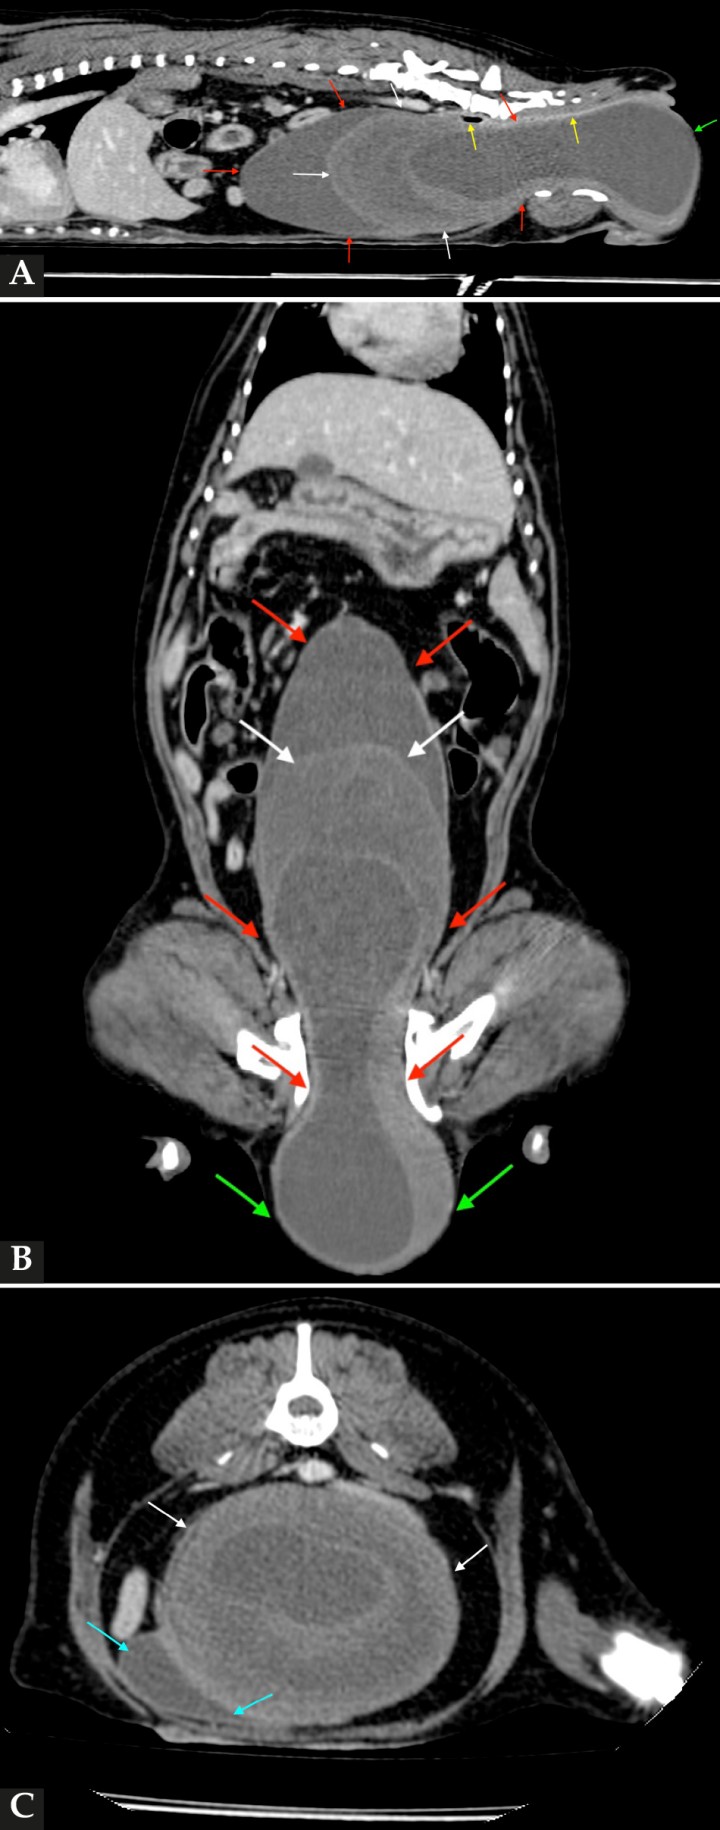

Para una mayor caracterización de la masa se realizó una tomografía computarizada (TC) (Fig. 4). En el estudio se observó, desde el vestíbulo vaginal, la vagina marcadamente distendida, con una estructura con contenido hipoatenuante (atenuación hasta 13 UH) y un halo externo asimétrico e hiperatenuante que no captaba contraste intravenoso. Esta estructura mostraba una pared craneal de 40 mm de espesor, que ocupaba todo el diámetro vaginal y presentaba una convexidad hacia craneal. Craneal a esta lesión, la vagina continuaba distendida con contenido hipoatenuante hasta el nivel del cuello uterino. La masa se extendía hacia la región perineal de manera bilateral con unas dimensiones aproximadas de 6 cm de altura x 7,6 cm de anchura x 22 cm de longitud. Estos cambios en la vagina provocaban un desplazamiento y una compresión marcada del colon descendente y del recto hacia dorsal y de la vejiga de la orina y uretra hacia craneoventral. Ambos cuernos uterinos se observaban levemente distendidos, de paredes irregulares, con contenido hipoatenuante. Ambos ovarios mostraban varias lesiones quísticas.

<p>Imágenes de TC de abdomen en ventana de tejidos blandos tras la administración de contraste intravenoso. (<strong>A</strong>) Plano sagital. (<strong>B</strong>) Plano dorsal. (<strong>C</strong>) Plano axial. Se observa la vagina marcadamente distendida desde el vestíbulo vaginal hasta el nivel del cuello uterino, con fluido en su luz (flechas rojas). Se observa en su luz una estructura con contenido hipoatenuante, con halo asimétrico e hiperatenuante (flechas blancas). Obsérvese cómo la masa provoca un desplazamiento y compresión del colon descendente y recto hacia dorsal (flechas amarillas) y de la vejiga de la orina y uretra hacia craneoventral y lado derecho (flechas azules). La masa protruye caudalmente sobre la región perineal, de manera bilateral (flechas verdes)</p>

Imágenes de TC de abdomen en ventana de tejidos blandos tras la administración de contraste intravenoso. (A) Plano sagital. (B) Plano dorsal. (C) Plano axial. Se observa la vagina marcadamente distendida desde el vestíbulo vaginal hasta el nivel del cuello uterino, con fluido en su luz (flechas rojas). Se observa en su luz una estructura con contenido hipoatenuante, con halo asimétrico e hiperatenuante (flechas blancas). Obsérvese cómo la masa provoca un desplazamiento y compresión del colon descendente y recto hacia dorsal (flechas amarillas) y de la vejiga de la orina y uretra hacia craneoventral y lado derecho (flechas azules). La masa protruye caudalmente sobre la región perineal, de manera bilateral (flechas verdes)

Los hallazgos fueron compatibles con una distensión vaginal marcada con una estructura intraluminal cavitaria compatible con un piocolpos/hidrocolpos secundario a un himen imperforado.